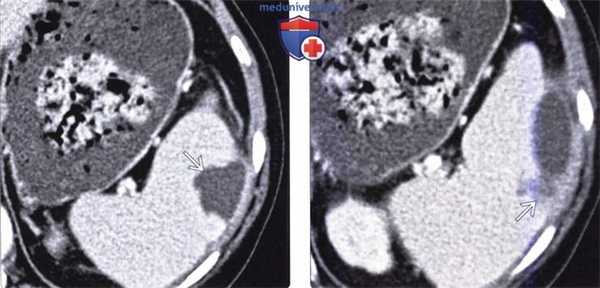

(Слева) На аксиальной КТ с контрастным усилением определяется многокамерное образование в селезенке, которое было верифицировано как пиогенный абсцесс. Такие большие абсцессы нетипичны для селезенки, особенно при отсутствии признаков первичного инфаркта.

(Справа) На аксиальной КТ с контрастным усилением у пациента с недавней травмой селезенки, у которого возник новый виток лихорадки, определяется скопление жидкости (уровень «жидкость-газ») окруженное «ободком», накапливающим контрастное вещество (абсцесс селезенки). Было выполнено чрескожное дренирование абсцесса, пациенту назначены антибиотики. (Слева) На аксиальной КТ с контрастным усилением у пациента со СПИД, обусловленным ВИЧ, с жалобами на снижение веса тела и лихорадку, визуализируются микроабсцессы по всей селезенке. Состояние пациента быстро ухудшилось, и он погиб; при вскрытии были обнаружены множественные туберкулезные абсцессы.